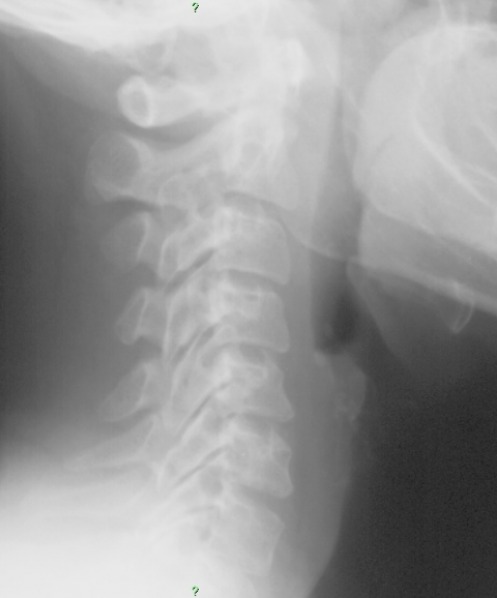

They key finding is best appreciated on the lateral view which shows circular radiolucent lesions within the posterior elements at multiple vertebral levels. There is also an expansile lesion at the posterior elements at C2-3. A solitary vertebral body lesion is appreciated at the anterior superior corner of the C6 vertebral body. The most likely differential considerations considering the patient age include metastatic disease and multiple myeloma. There are other conditions which may produce multiple lytic lesions of multiple bones. Cystic angiomatosis or hemangiomatosis and lymphangiomatosis are both RARE conditions characterized by disorder of hemangiomas and the lymphatic system respectively producing cystic bony lesions in multiple locations. Patients with both of these conditions are usually diagnosed at a younger age due to associated visceral lesions. Other conditions which may present with multiple lytic skeletal lesions include polyostotic fibrous dysplasia and Paget's disease, unlikely in this case due to the appearance of the lesions, eosinophlic gramuloma, unlikely due to the patient's age.

Here are magnified and negative views of the lateral cervical which may make it easier to see some of the lesions.